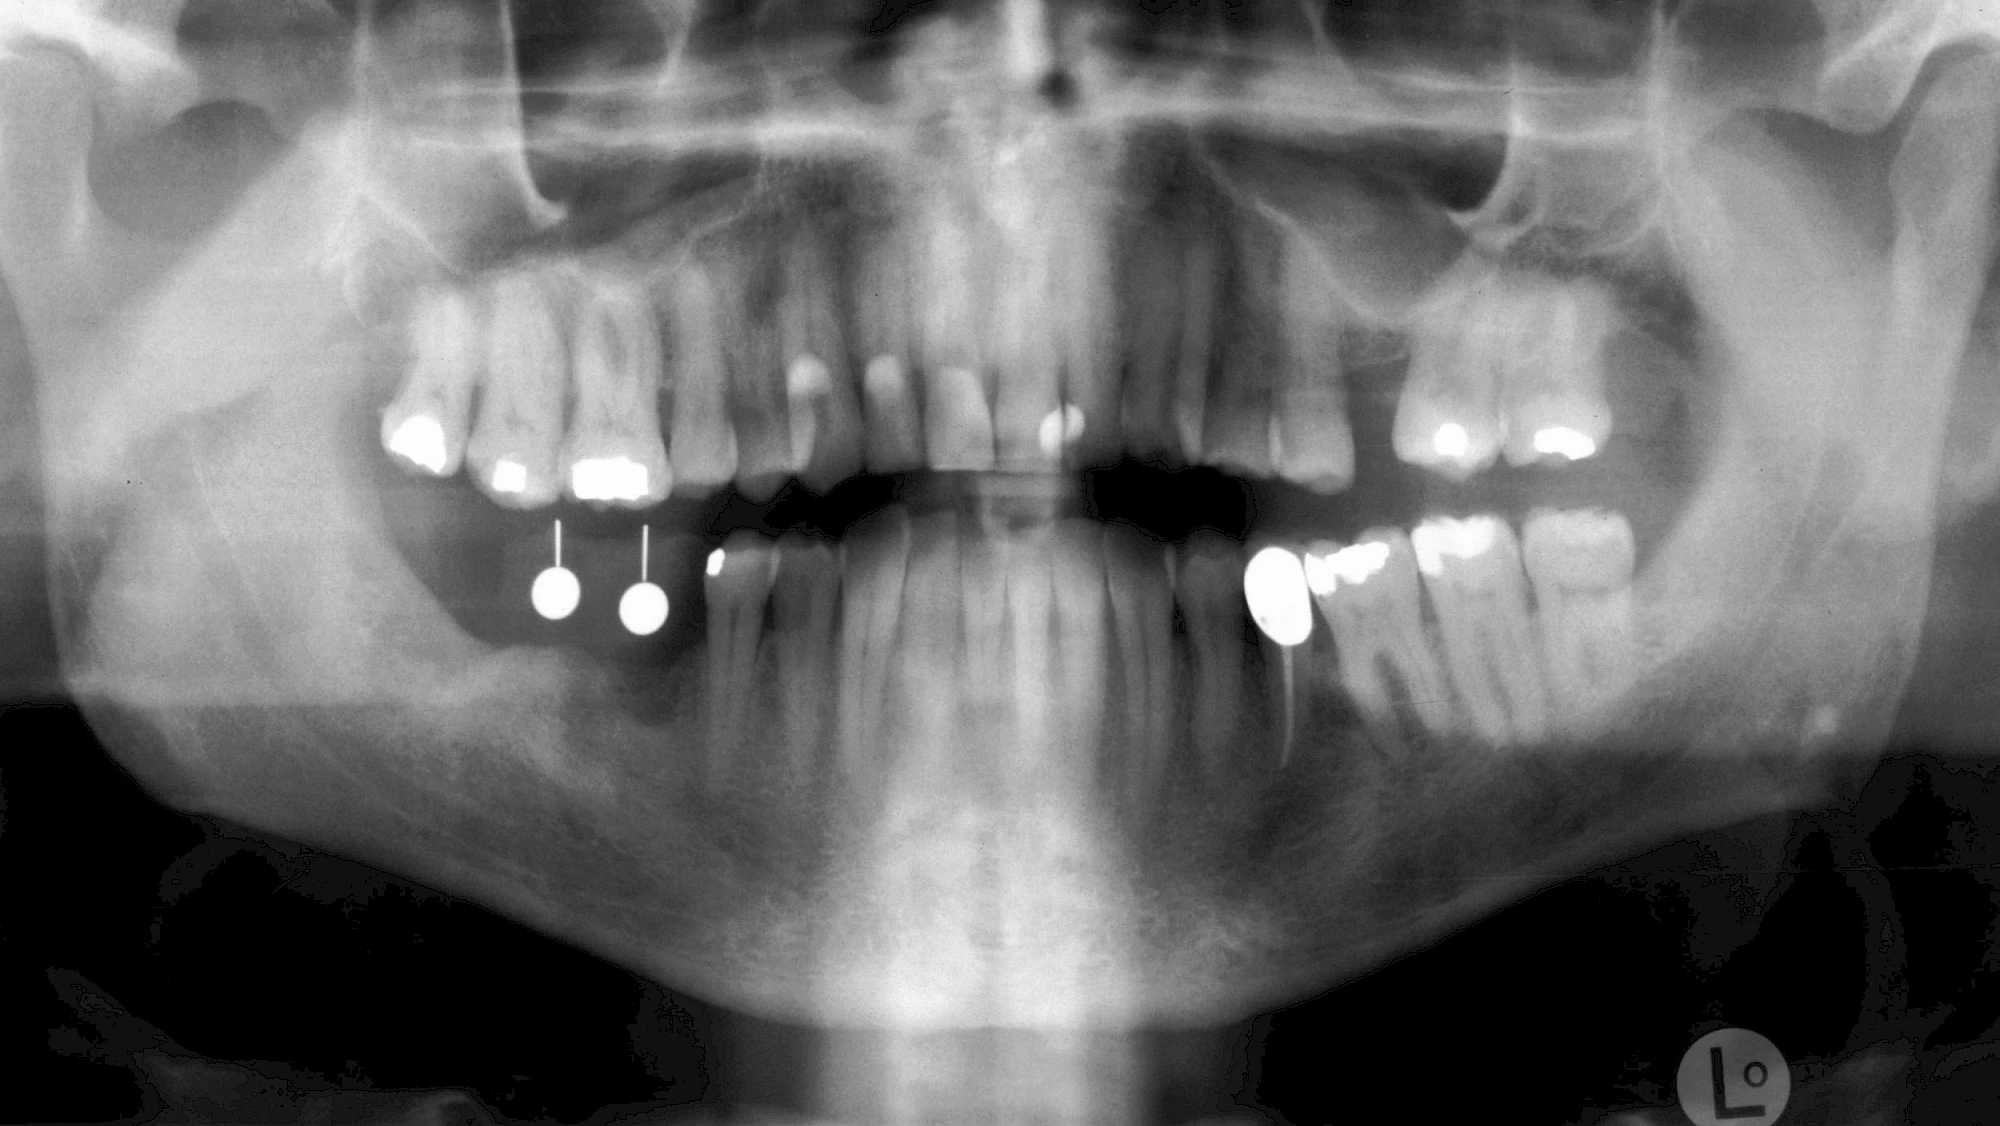

Implantatplanung

Damit Implantate an der richtigen Stelle im Kieferknochen platziert werden könen, gibt es heute vielfältige Möglichkeiten der Planung. In vielen Situationen kann die Erfahrung des Zahnarztes ausreichend sein.

Nicht selten ist jedoch auch eine technisch aufwändigere Vermessung im Vorfeld sinnvoll, z. B.:

- Wenn sich der Kieferknochen abgebaut hat

- Wenn der Nervverlauf im Unterkiefer beachtet werden muss

- Wenn die Ausdehung der Kieferhöhle im Oberkiefer beachtet werden muss

- Wenn wenige Restzähne keine gute Orientierung erlauben

In diesen Fällen kann die Planung mittels verschieden aufwendiger Röntgen-Techniken (Übersichtsaufnahme, DVT) ggf. unter Zuhilfenahme speziell angefertigter Planungsschablonen sinnvoll sein.